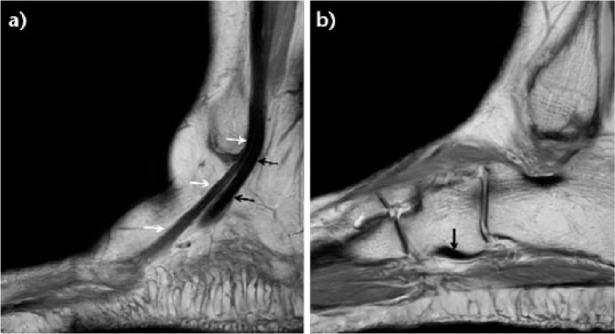

腓骨肌腱的病理异常是后足外侧疼痛和功能障碍的一个未被充分认识的原因,可能难以与外侧踝关节韧带损伤相区分。腓骨肌腱位于小腿外侧间室,是足部主要的外翻肌,起外侧踝关节稳定器的作用。肌腱病变大致可分为三类:肌腱炎和腱鞘炎、肌腱半脱位和脱位,以及肌腱劈裂和撕裂。这些病变可能与踝关节不稳定、后足畸形以及诸如低位腓骨短肌或第四腓骨肌等异常解剖结构有关。全面的临床检查应包括评估足型(高弓足或扁平外翻足)、在抗阻踝关节背屈和外翻时触诊后踝沟处的腓骨肌腱以及测试外侧踝关节韧带。包括X线片、超声和磁共振成像在内的影像学检查将有助于明确诊断。这些疾病的治疗建议主要基于病例系列研究和专家意见。本综述的目的是总结目前对腓骨肌腱解剖结构和诊断评估的认识,并介绍腓骨肌腱损伤的保守和手术治疗方案。引用本文:2017;2:281 - 292。DOI: 10.1302/2058 - 5241.2.160047。